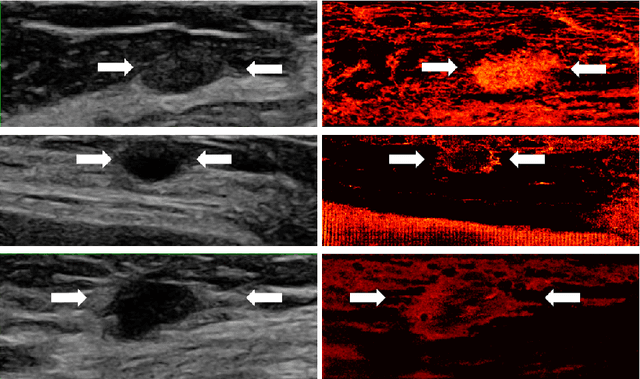

Abstract:Breast cancer is the most common malignancy in women. Mammographic findings such as microcalcifications and masses, as well as morphologic features of masses in sonographic scans, are the main diagnostic targets for tumor detection. However, improved specificity of these imaging modalities is required. A leading alternative target is neoangiogenesis. When pathological, it contributes to the development of numerous types of tumors, and the formation of metastases. Hence, demonstrating neoangiogenesis by visualization of the microvasculature may be of great importance. Super resolution ultrasound localization microscopy enables imaging of the microvasculature at the capillary level. Yet, challenges such as long reconstruction time, dependency on prior knowledge of the system Point Spread Function (PSF), and separability of the Ultrasound Contrast Agents (UCAs), need to be addressed for translation of super-resolution US into the clinic. In this work we use a deep neural network architecture that makes effective use of signal structure to address these challenges. We present in vivo human results of three different breast lesions acquired with a clinical US scanner. By leveraging our trained network, the microvasculature structure is recovered in a short time, without prior PSF knowledge, and without requiring separability of the UCAs. Each of the recoveries exhibits a different structure that corresponds with the known histological structure. This study demonstrates the feasibility of in vivo human super resolution, based on a clinical scanner, to increase US specificity for different breast lesions and promotes the use of US in the diagnosis of breast pathologies.